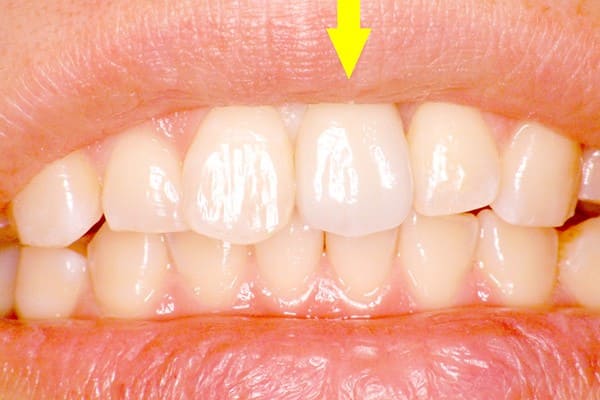

口腔内の状態にもよりますが、下の写真のように、患者様ご自身の歯と、ほとんど区別のつかないぐらいの歯を回復します。

50代女性の症例

黄色矢印の歯がインプラントです